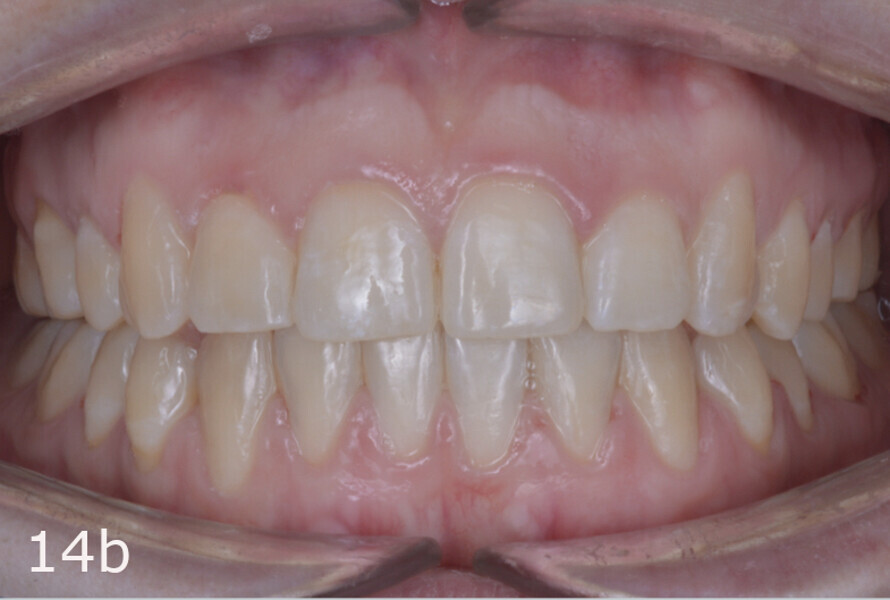

The total treatment time was 15 months. An Angle Class I relationship was established along with adequate anterior and canine guidance, establishing a functional occlusion. This not only ensures optimal masticatory function but also protects the teeth and the temporomandibular joint from excessive force. Maxillary and mandibular fixed retention were installed at the end of the treatment (Figs. 13–19).